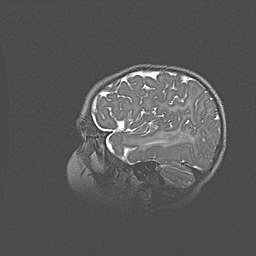

Множественные кисты обоих полушарий головного мозга, наибольшая из них в правой затылочной области. Ассиметричная атрофическая гидроцефалия.

Возраст: 7 месяцев

Вес: 5660 г

Пол: мужской

Окружность головы: 41,5 см

Срок гестации: 28-29 недель

Кисты головного мозга развиваются в результате многоочаговых некрозов вещества мозга и возникают вследствие перенесенной перинатальной инфекции, менингитов, энцефалитов, асфиксии, родовой травмы, расстройств мозгового кровообращения различного генеза. Образованию кист в веществе головного мозга плодов и новорожденных способствуют такие факторы, как высокое содержание в нем воды, недостаточная (или отсутствие) миелинизация и слабая астроглиальная реакция на повреждение.

Кисты могут сочетаться с гидроцефалией и другими поражениями головного мозга.